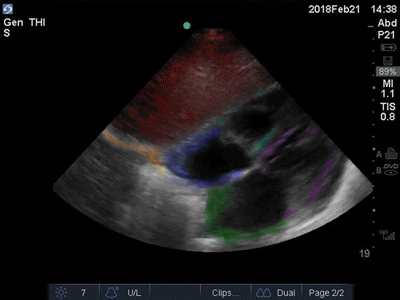

Colorized Atlas - Subxiphoid - Colorized 2

Subxiphoid Red: Liver. Orange: Diaphragm. Blue: Right Atrium, Teal: Right Ventricle, Green: Left Atrium,Purple: Left Ventricle Images: Dr. Lindsay Davis, Dr. Hannah Kopinski. Image Editing: Michael Amador and Dr. Matthew Riscinti